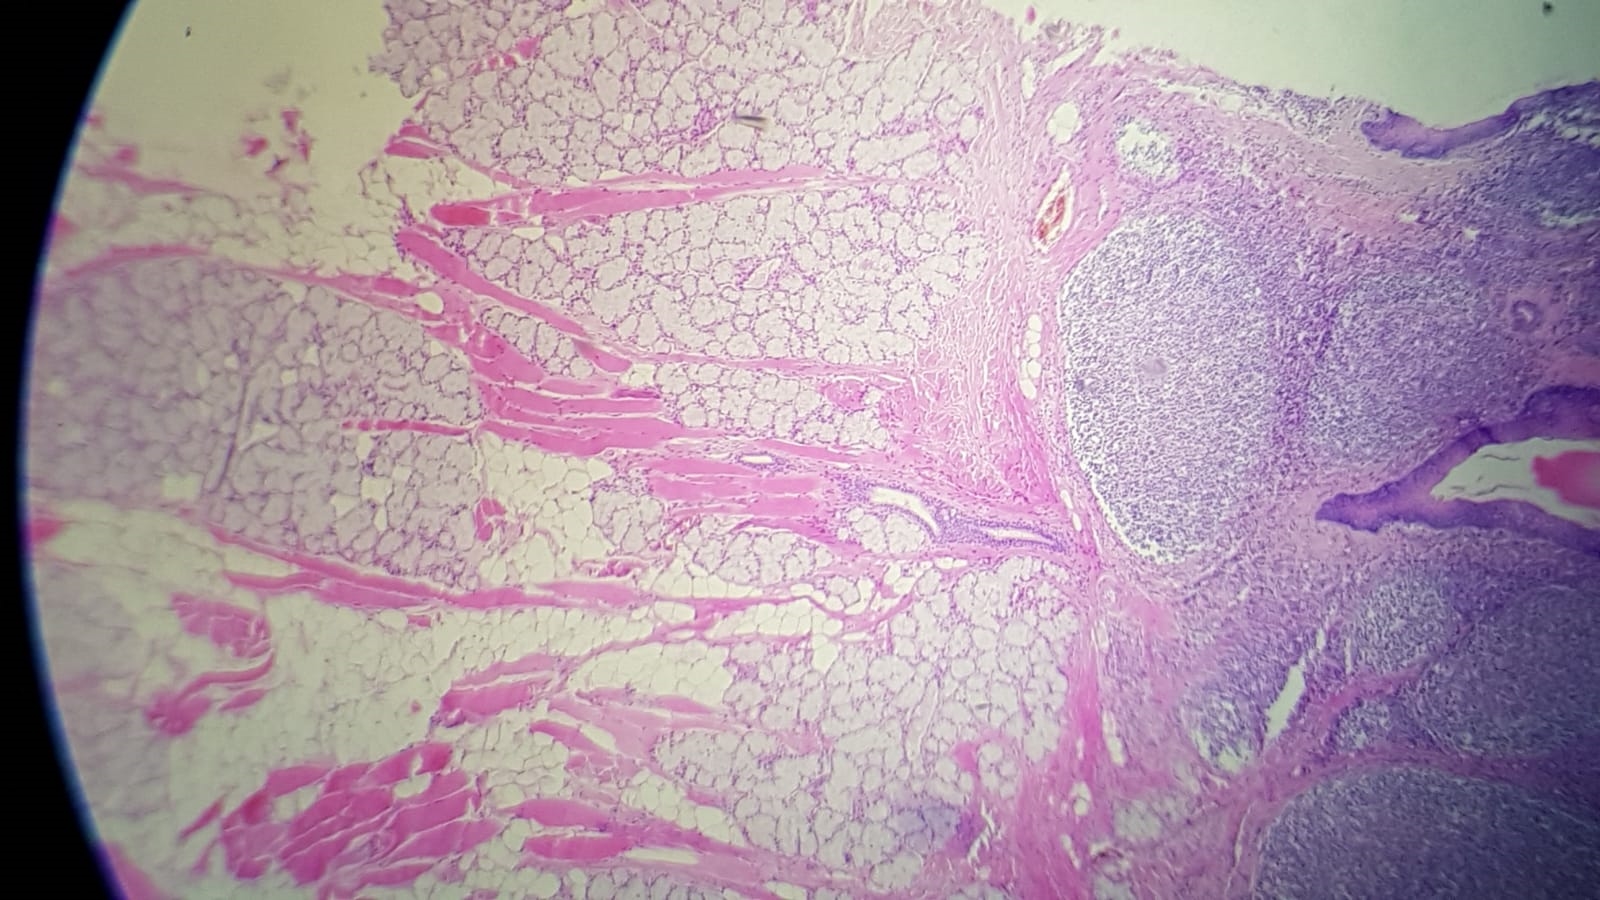

Ich wollte einmal versuchen, ob man aus Supermarkt Ware brauchbare histologische Präparate anfertigen kann. Als Testobjekt habe ich mich für eine Schweinezunge entschieden und das Resultat ist erstaunlich gut. Fixiert wurde in 4% Formalin und mit HE gefärbt.

Das Präparat wurde aus dem hinteren Teil der Zunge angefertigt. An der Oberfläche findet man ein mehrschichtig unverhorntes Plattenepithel. Darunter liegt die Zungenmandel (Tonsilla Lingualis) und man erkennt zahlreiche Lymphozyten. Die Zungenmandel ist Teil des Mucosa assoziierten lymphatischen Gewebes (MALT). Unter ihr befinden sich Bindegewebe, zahlreiche muköse Drüsen mit Ausführungsgängen und quergestreifte Skelettmuskulatur.

Die Bilder 1 und 2 sind Übersichtsaufnahmen. Man sieht das Epithel, Zungenmandel mit Lymphfollikel, Drüsengewebe, quergestreifte Muskulatur, Gefäße, Drüsenausführungsgänge und Bindegewebe.